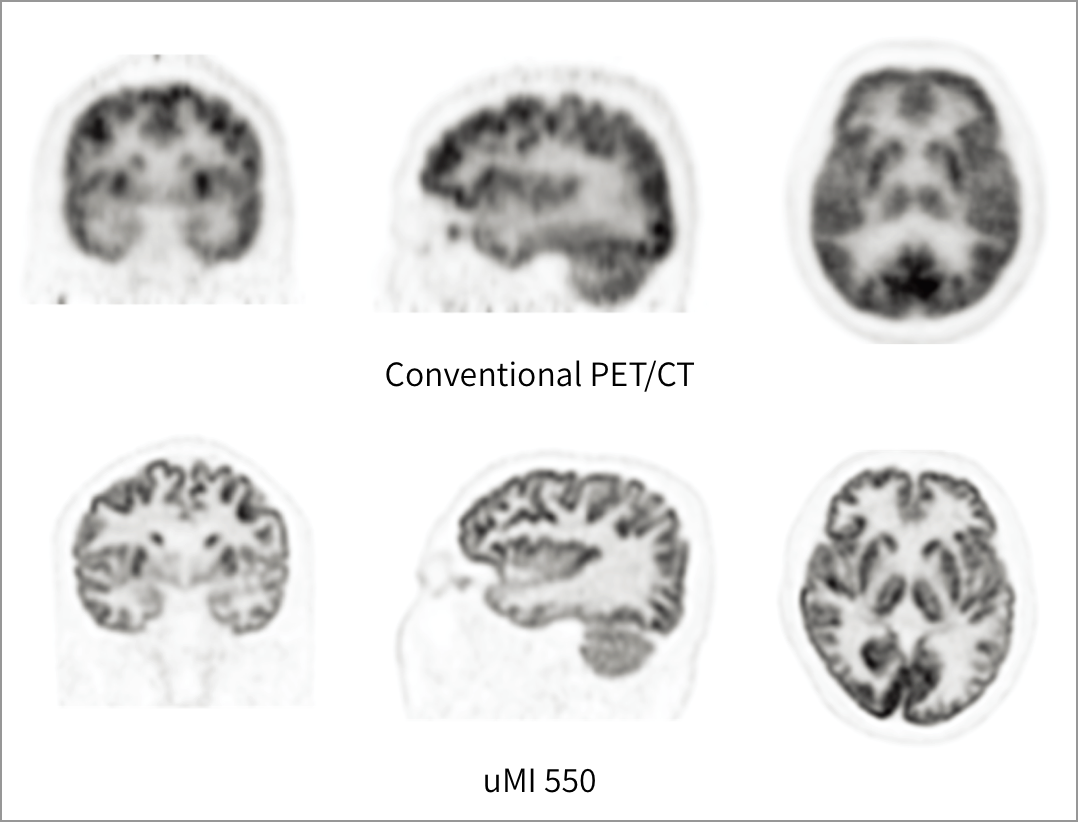

uMI 550 makes the state-of-art digital PET technology attainable to more customers. With the unique Integrated-Light-Guide Digital PET detector, uMI 550 provides 2.9mm NEMA resolution. The 80-slice CT system with Z-Detector enables diagnostic CT images with high spatial resolution and improved low contrast detectability.